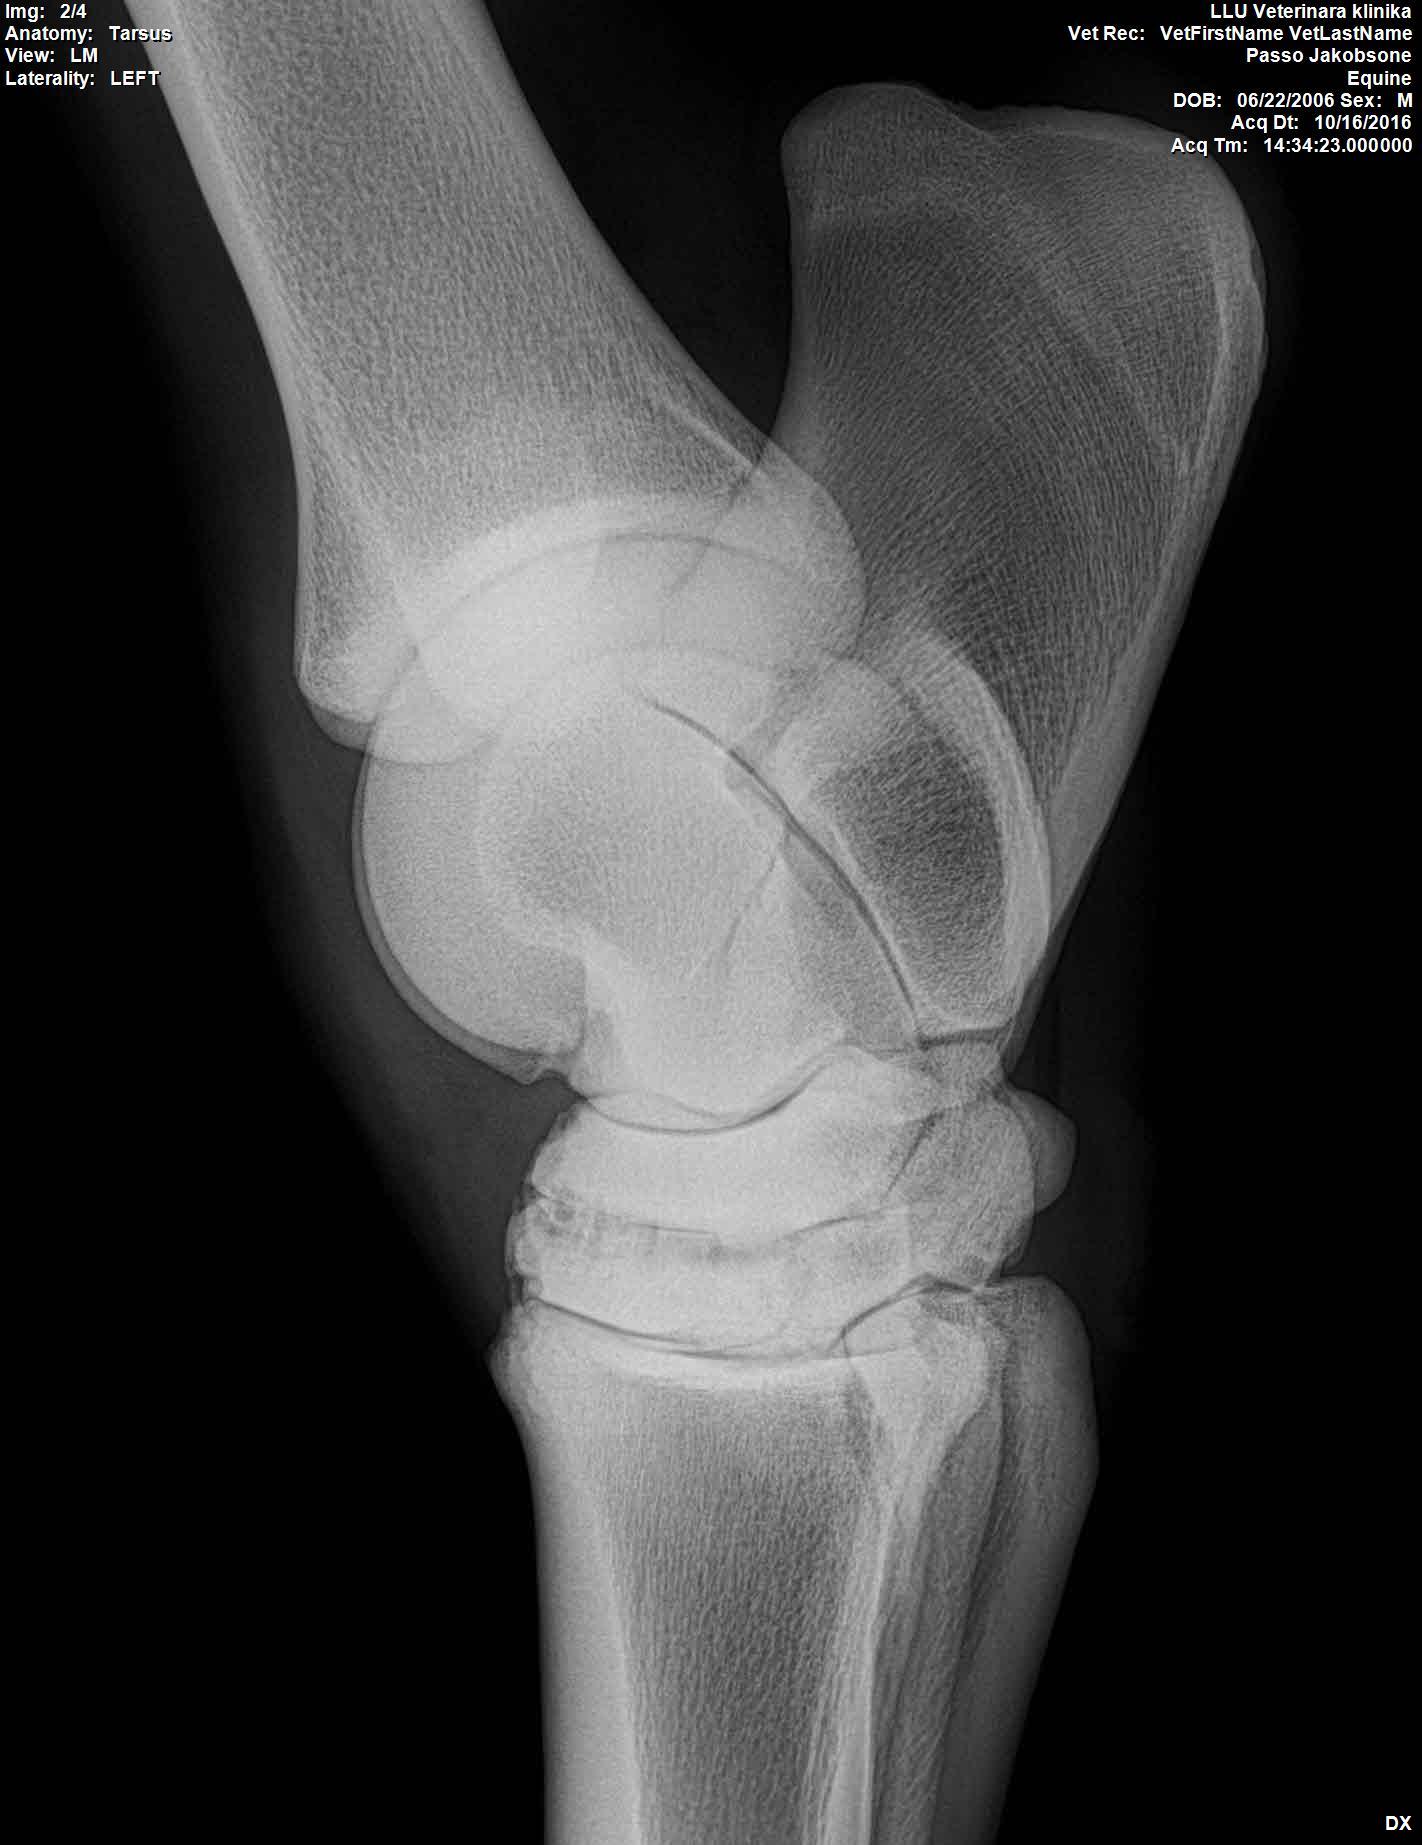

U majei loshadi ( 10 let) kastrat, v proslom godu obnaruzili spat I sdelali kurss Tildren, 16.10.2017. ehso odin kurss, daju polgoda eto http://ru.eggersmann.info/432_/132_Profi_Gelenk_aktiv.html, I vot kakije u loshadi rentgeni po datam. Prigaju do 110 cm, edu na sorevnavanije, idjot on horosho. esli stojal v bokse , snachala hromaet,no potom 2-4 minuti v risi i prohodit. Ja bi hotela prigatj vishe,no bojus ,mozno li. Letom dva raza bila ,chto v trenirovke zahramal ochen silno,no cerez paru chasov ,vsjo proslo.